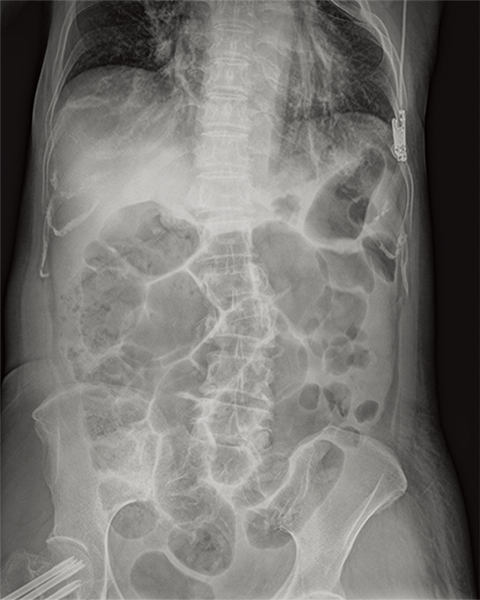

Multiple body parts supported

Abdomen

Dynamic Visualization II

Optimizes image quality using latest Exposure Data Recognizer

Advanced recognition algorithms using automatic  calculations of estimated 3D image data, identify the body part required and adjusts contrast, density and enhancement for optimised image display. (Option)

Comparison of Dynamic Visualization II vs. conventional processing images (Lumbar Spine)

Comparison of Dynamic Visualization II vs. conventional processing images (Hip Joint)